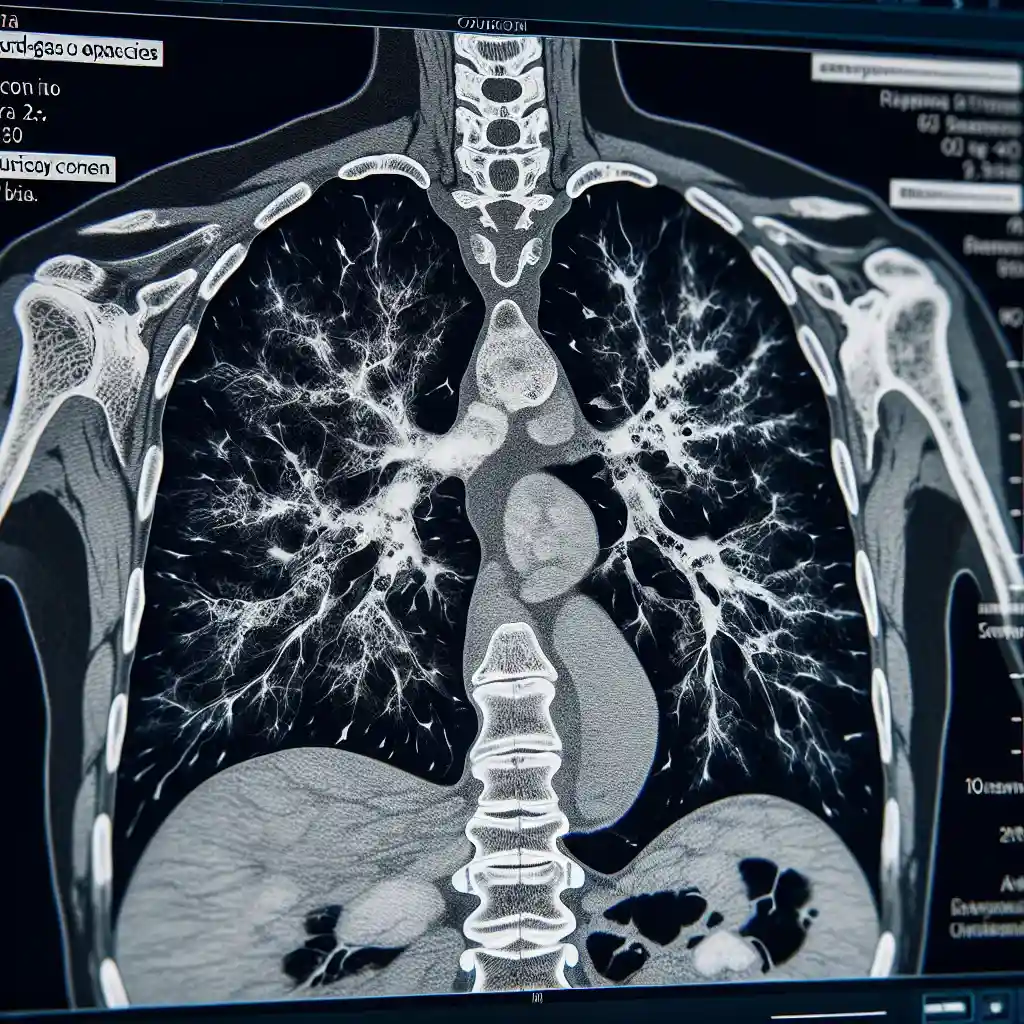

КТ лёгких: что означают КТ-1, КТ-2, КТ-3 и КТ-4

Компьютерная томография лёгких (КТ лёгких) является одним из основных методов диагностики заболеваний дыхательной системы. С её помощью можно детально оценить состояние лёгочной ткани, выявить очаги воспаления, фиброза или других патологий. В медицине используется классификация КТ-0, КТ-1, КТ-2, КТ-3 и КТ-4, которая отражает степень поражения лёгких и помогает врачам определить подходящую тактику лечения. В этой статье подробно разберём, что означают эти обозначения и как интерпретировать результаты диагностики.